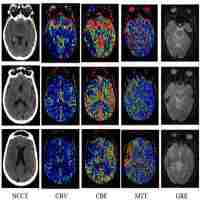

| Abstract | The inclusion of dynamic contrast-enhanced computed tomography (CT) or CT perfusion (CTP) scan into the imaging workup for acute stroke patients is widespread. Along with vessel occlusion status from CT angiography, CTP provides pathophysiological information a non-contrast CT cannot provide during the hyperacute stages of cerebral ischemia. Measurement of parenchymal perfusion at the capillary level can be used to characterize tissue viability, a target for thrombolysis. Further, CTP is useful for the detection of blood brain barrier disturbances with the permeability surface area product parameter (PS). Although new to stroke imaging, PS has diagnostic and prognostic implications for primary hemorrhage and secondary hemorrhagic transformation of ischemic stroke. The purpose of this article is to provide an overview of the CTP imaging concepts and their uses for imaging in stroke. |

| Subject Keyword | Computed tomography perfusion Acute stroke Cerebral blood flow Cerebral blood volume Permeability surface area product Hemorrhagic transformation hemorrhage Vascular Surgery Neurosurgery Cardiology Neurology Neurosciences |